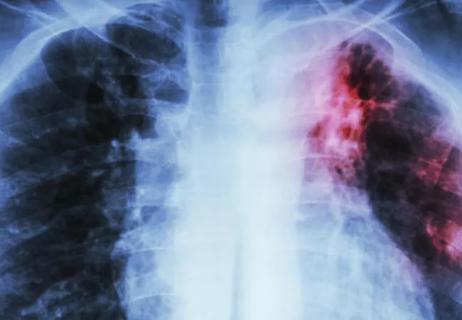

Figure 1. A female patient with a history of recurrent pneumothoraces and a subtle, easily overlooked cyst, received a diagnosis of Lymphangioleiomyomatosis (LAM) through a surgical lung biopsy performed concurrently with pleurodesis.

Real-life medical practice often presents challenges, and CT imaging may reveal ambiguous or atypical findings that differ from textbook depictions. From our experience, in the early stages of LAM, tiny cysts can be easily overlooked (Figure 1). Conversely, advanced cases may sometimes resemble other advanced-stage cystic damage, making differentiation challenging (Figure 2).

Figure 2. A female patient in an advanced stage of cystic lung disease was diagnosed with Lymphangioleiomyomatosis (LAM), supported by evidence of extrapulmonary features, including AML (angiomyolipomas), chylous effusion, and an exceptionally elevated VEGF-D level exceeding 3000.